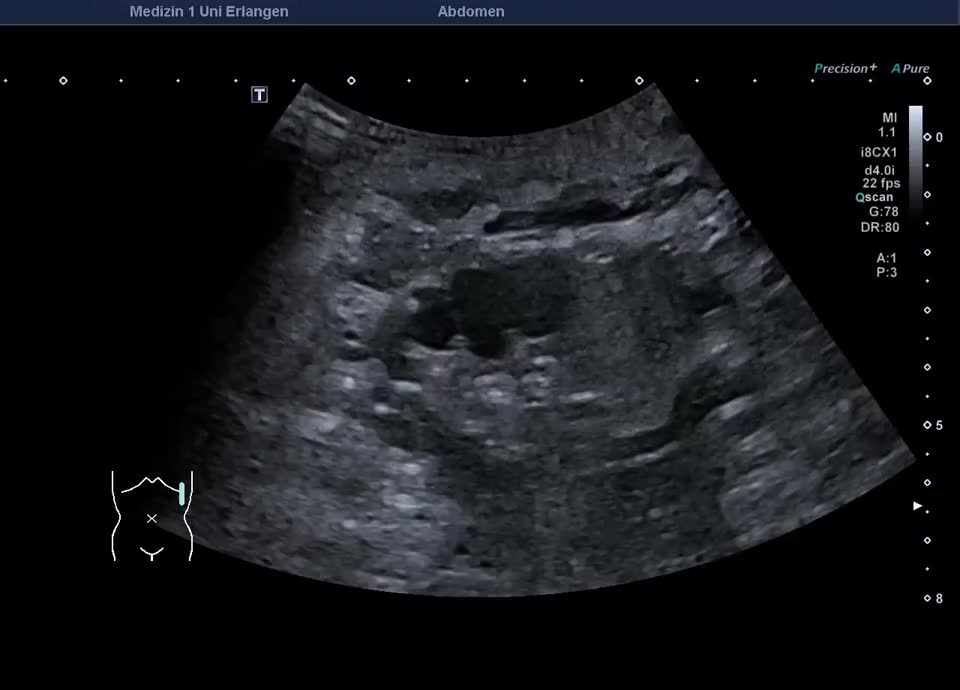

• Bosniak III cyst in the left kidney (video)

• Bosniak III cyst in the left kidney (color Doppler)